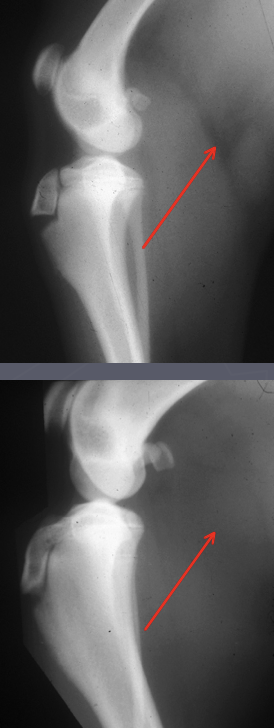

Which is normal and which is abnormal?

-top is normal; can see the fascial plane

-bottom is abnormal; fascial plane is no longer visible